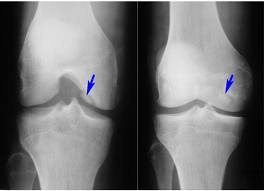

ДИАГНОСТИКА

Диагноз устанавливает врач после расспроса и осмотра больного. Обязательно проводятся лабораторные и инструментальные методы обследования: исследование крови, рентген, сцинтиграфия, МРТ, диагностическая артроскопия.

Медицинские процедуры, проводимые при заболевании болезнь кёнига: Клинический анализ крови, С-реактивный белок, Биохимический анализ крови, Рентген, Сцинтиграфия костей, Магнитно-резонансная томография, Артроскопия